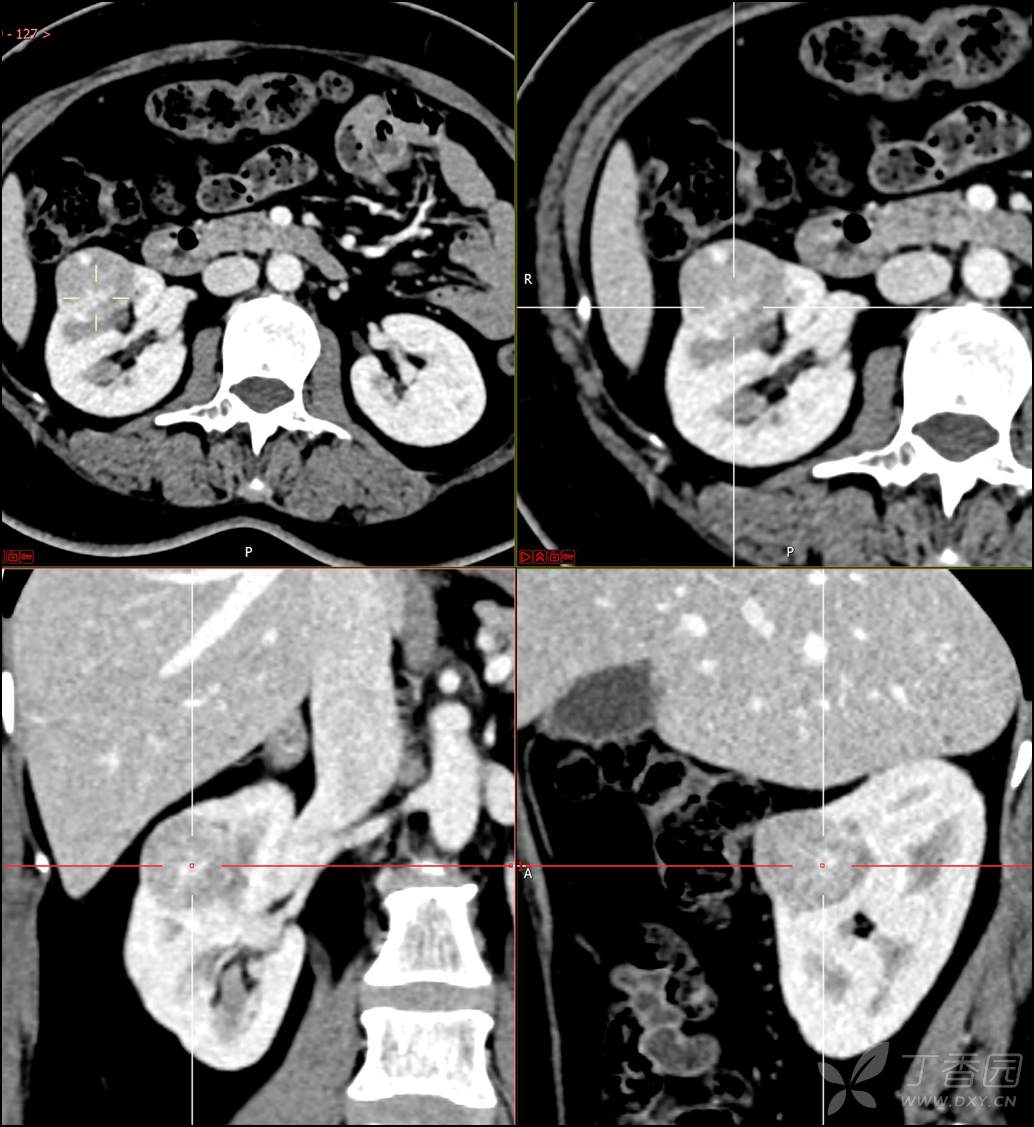

【影诊笔记516】中年女性,检查发现肾占位2周就诊~『嗜酸细胞腺瘤』

主诉:检查发现肾占位2周

简要病史:患者2周前体检发现肾实质性占位,无腰痛,无血尿,无尿频、尿急、尿痛,无发热,在外未行特殊治疗。患者为行进一步治疗就诊于我院,门诊以“肾占位性病变 ”收入我科,患者自发病以来,神志清,精神可,小便如上所述,大便正常,体重无显著变化。